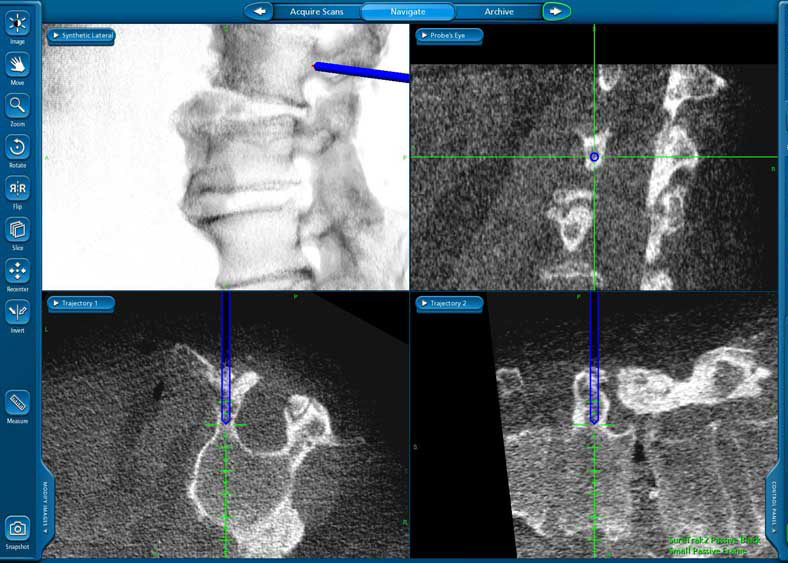

Using radiographic navigation, a diagnostic quality CT scan can be created in the operating room. This scan is then linked to the instruments allowing them to be visualized "real-time" on the CT scan images. The surgery can then be performed through small percutaneous incisions accessing the spine deep inside the body without having to expose it directly.